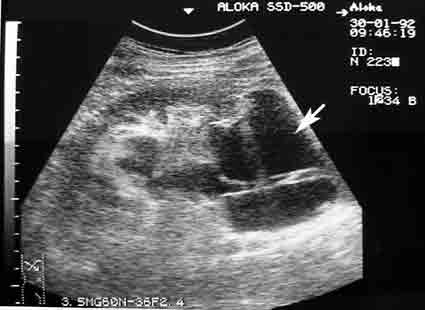

Архивные сонограммы, редкий случай.

На первый взгляд многокамерная киста.

Полостное образование с анэхогенным содержимым циркулярно охватывающее проксимальный отдел мочеточника, вызывающее уростаз. Предположу, что его можно назвать периуретеральная киста .

Почечная артерия проходит в почечной парапельвикальной кисте.

Пациент был оперирован, урологи были удивлены не меньше моего.

Жаль, что тогда не было ЦДК.